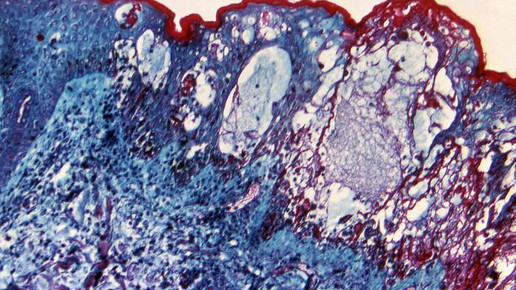

Seit Längerem ist ein Zusammenhang zwischen Gürtelrose und Windpocken bekannt. Der erste Kontakt mit dem Erreger Varizella zoster findet meist im Vorschulalter durch eine Tröpfcheninfektion statt. Nach etwa zwei Wochen entsteht ein juckender Ausschlag auf der Haut. Sind die Windpocken überstanden, wandern die Viren in die Hirnnerven und Nervenwurzeln des Rückenmarks. In den Nervenknoten verbleiben sie in einer Art „Schlaf“. Werden sie durch Stress, UV-Strahlung, ein schwaches Immunsystem oder durch das erreichte höhere Alter reaktiviert, entsteht eine Gürtelrose. Behandelt wird lokal mit Lösungen oder Salben, die einen austrocknenden Effekt haben und systemisch mit Virustatika wie Aciclovir, Valaciclovir sowie Brivudin.